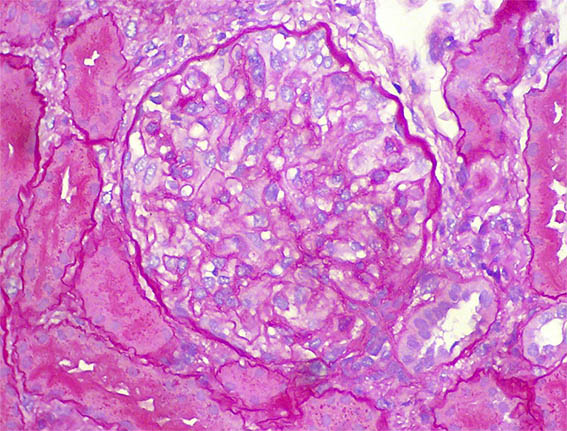

Figura 3.

H&E, X400.

Figura 4. H&E, X400.